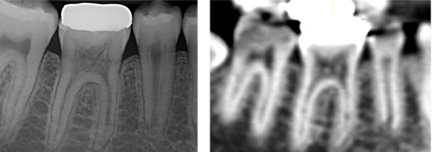

radiographic assessment prior to dx

2 angles (30 degrees mesial or distal beam shift)

or CBCT

Parallax – find out if resorption buccal, lingual or external/internal

* If resorption moves – external

* If fixate/centre in tooth – internal

Single biggest thing to aid dx – internal balloons out from internal aspect of canal

* Parallel lines of RCS lost (tramlines) = INTERNAL

* External = superimposition of resorption – can still see tramlines of pulp, internal aspect of RCS intact